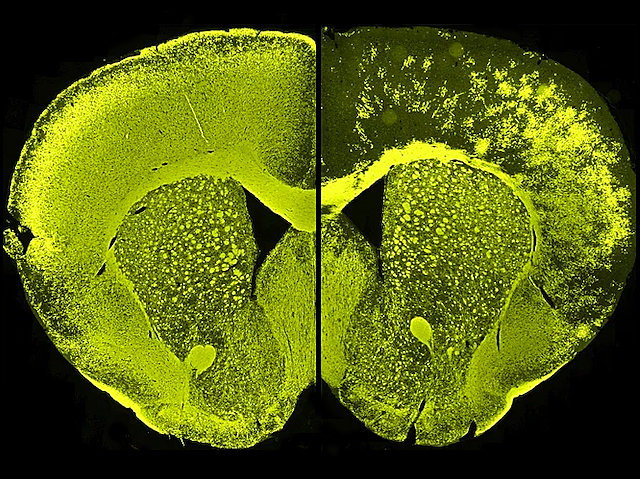

Ageing Insulation

Link between loss of myelin – the insulating sheath around nerves – and ageing revealed

Signals speed through your nerves thanks to myelin sheaths – insulation that wraps around your nerves like plastic around wires. In ageing brains, defects in myelin sheaths occur deep in the brain. A mouse model of this reveals subsequent behavioural problems. Determining the effects on cognition, however, is trickier. Why? Because cognition experiments rely on readouts of physical abilities, which also depend on myelinated nerves. Researchers, therefore, looked at mutant mice lacking a vital myelin sheath protein, Plp1, in stem cells of the forebrain; fluorescence microscopy of mutant brain tissue (pictured, right) revealed loss of Plp1 specifically in the forebrain compared with normal mice (left). These mice had myelin defects similar to ageing brains but intact physical abilities, which allowed cognition experiments. These revealed problems with executive function, that is, processes that control behaviour to achieve certain goals. This has implications for ageing brains but also neuropsychiatric and myelin-related conditions.